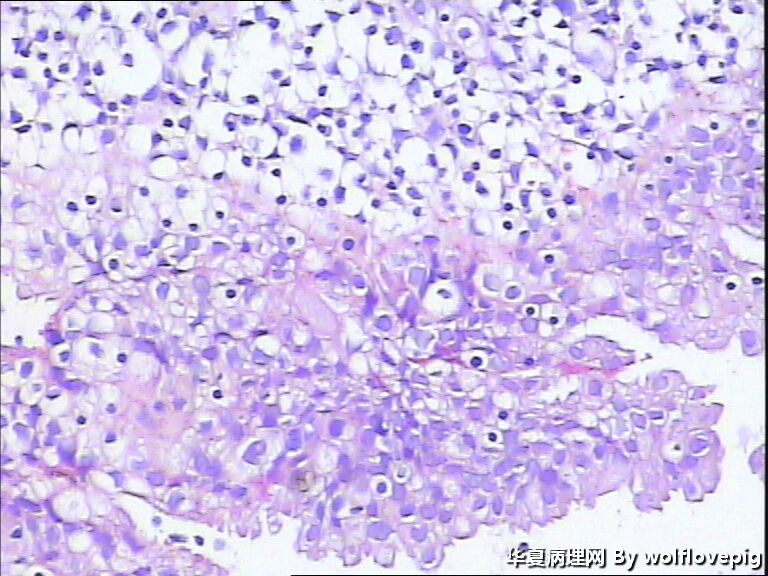

40y,阴道不规则流血10+天

流血期子宫内膜,这些变化都是化生,不怕

分泌期宫内膜伴嗜酸细胞化生

乳头状化生,嗜酸细胞化生,透明细胞化生

分泌期宫内膜伴嗜酸细胞、乳头状化生

医源性改变(药物等)。

是一种化生性改变,问题不大。